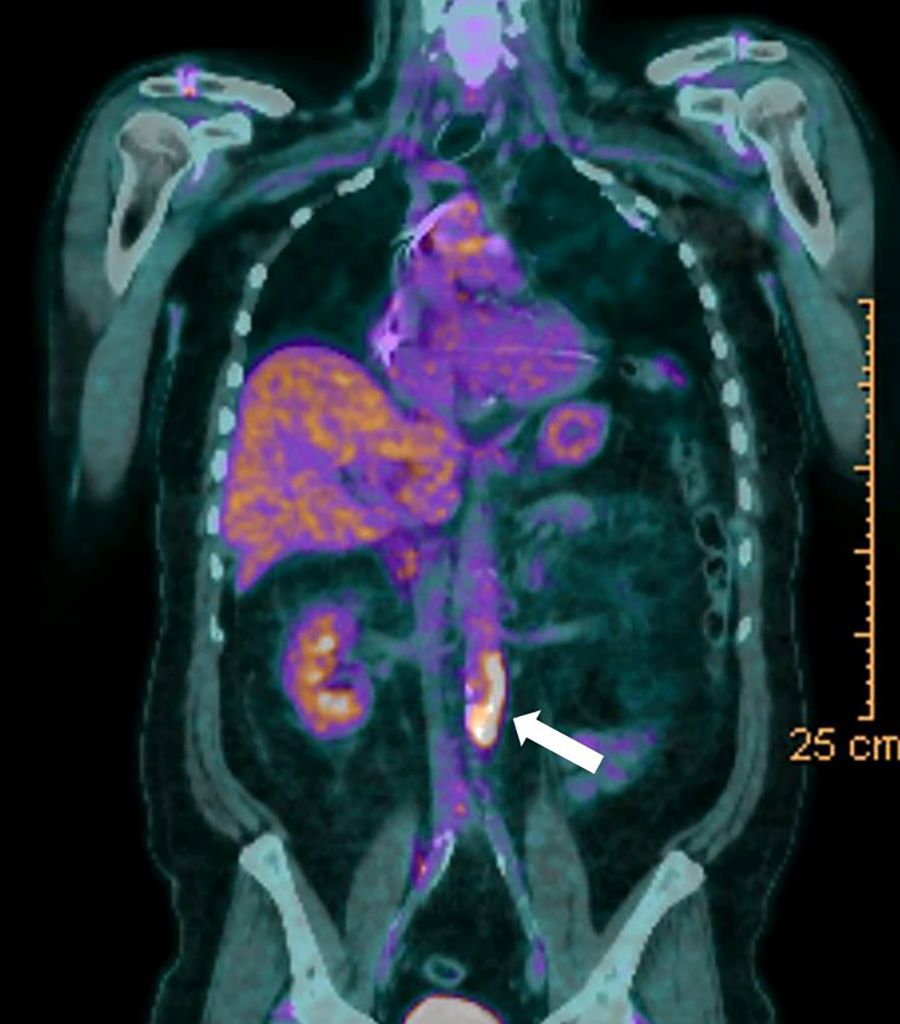

TEP scan (PET scan)

Tomographie à Émission de Positons

Il s’agit d’un examen d’imagerie performant, utilisant une technique moléculaire, pour analyser le métabolisme et l’anatomie des organes grâce au scanner qui est couplé

Cet examen détecte dans l’organisme des lésions cancéreuses, infectieuses ou inflammatoires, qui consomment du sucre en excès (métabolisme du glucose) ; cet examen permet aussi de suivre l’efficacité de certains traitements

⬇ image de Pet scan en faveur d’une inflammation de l’aorte abdominale visualisée par la captation intense du traceur (fléche blanche)